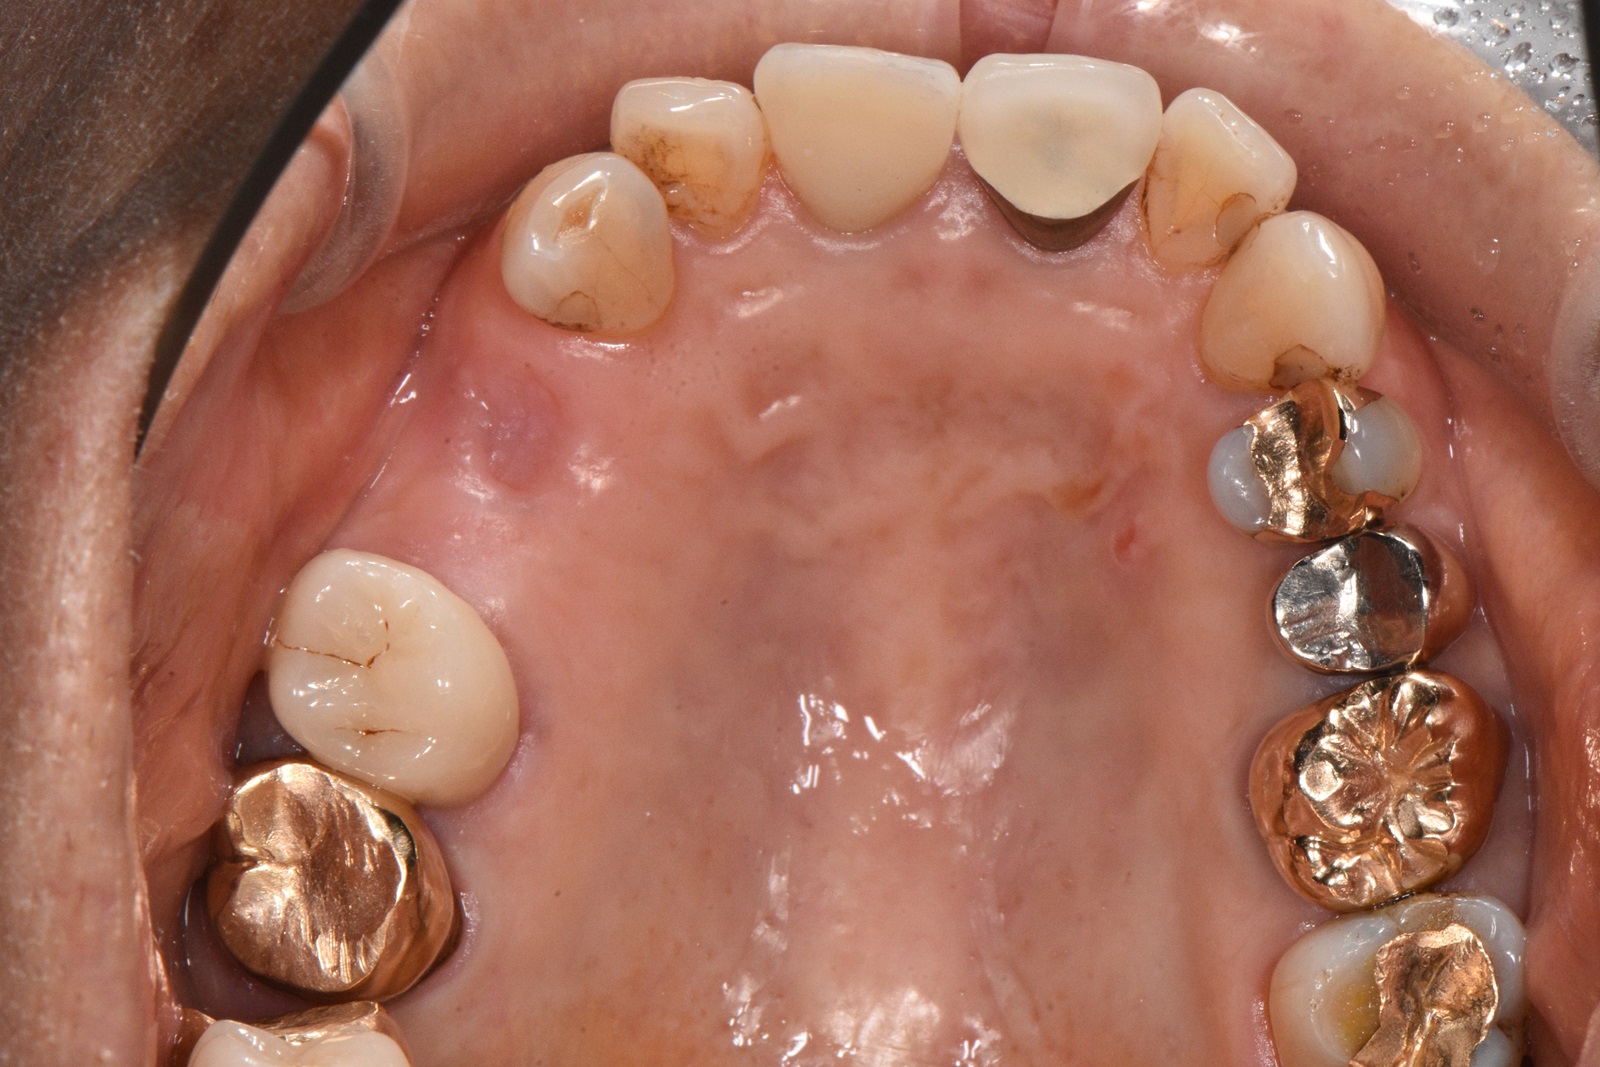

• 治療前

• 治療後